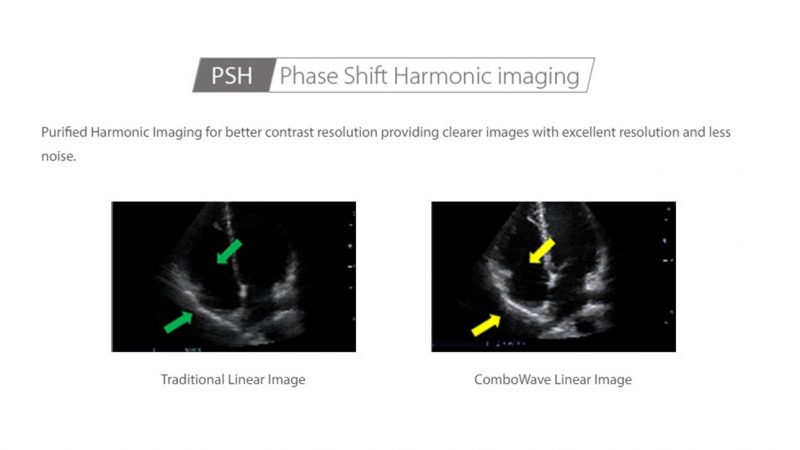

- PSHI (Phase Shift Harmonic Imaging) Purified Harmonic Imaging for better contrast resolution providing clearer images with excellent resolution and less noise.